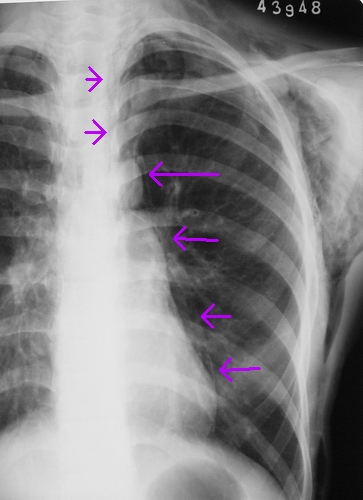

患者,女,18岁。气喘气促多年,加剧半天。摄片如下:

左侧气胸、皮下气肿

慢性支气管炎并肺气肿,左侧气胸、皮下气肿。

左侧气胸、皮下气肿。纵隔气肿。

左侧胸壁、腋窝、颈部及右侧颈部皮下软组织内示斑片状、条状低密度气体影,四天后复查片明显吸收好转。